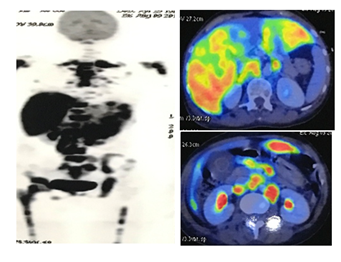

Screening for malignancy extension was performed. PET-CT scan showed multiple metastatic of hypermetabolic lymph node in bilateral supraclavicular, anterior mediastinum, paratrachea, tracheobronchial, subcarina, bilateral hilus, phrenic, coeliac, periporta, perigastrica, paraaorta, aortocava, pericava, prevertebra, mesenteric, and right parailiaca. Both hepatic lobes also showed diffuse metastase. Lytic and sclerotic lesion with destruction were seen in vertebra cervical I and II, almost all thoraco-lumbal-sacral, part of right and left costae, sternum, bilateral clavicula, bilateral scapula, bilateral humerus, pelvis, and bilateral femur suggested as bone metastases (Figure 5). Chemotherapy was planned on this case, however, one week later, patient died following acute respiratory distress syndrome due to pneumonia.

Figure 5 PET-CT scan showed multiple metastatic of lymph node in neck, chest, and abdomen. Liver and bone also showed diffuse metastases.